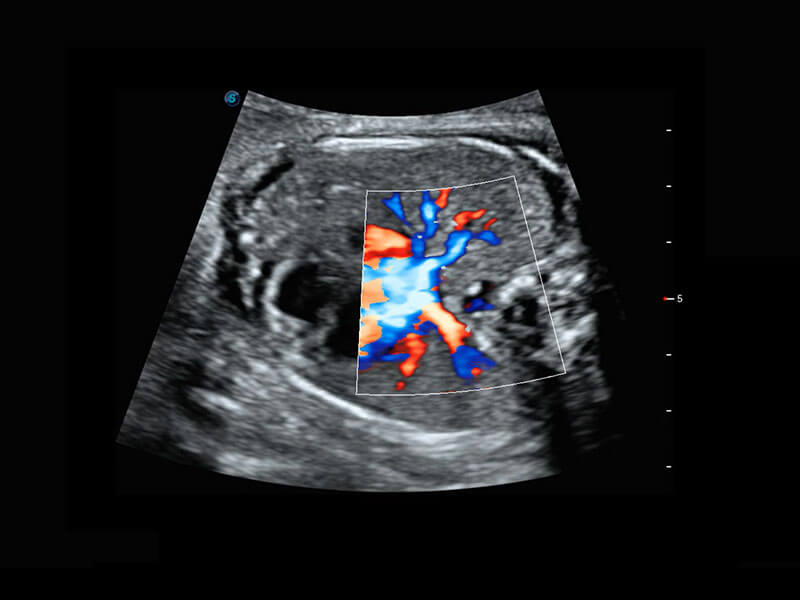

• 胎儿体循环

早孕筛查

P60在胎儿早孕期超声筛查中为您带来优异的图像质量。